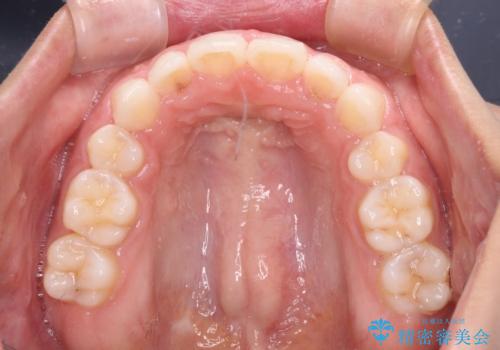

目立たない装置で横顔のシルエットを改善 ハーフリンガルでの抜歯矯正

- 口元の突出感を気にして来院された患者様です。

上下左右の第一小臼歯4本を抜歯して口元を下げる治療計画としました。